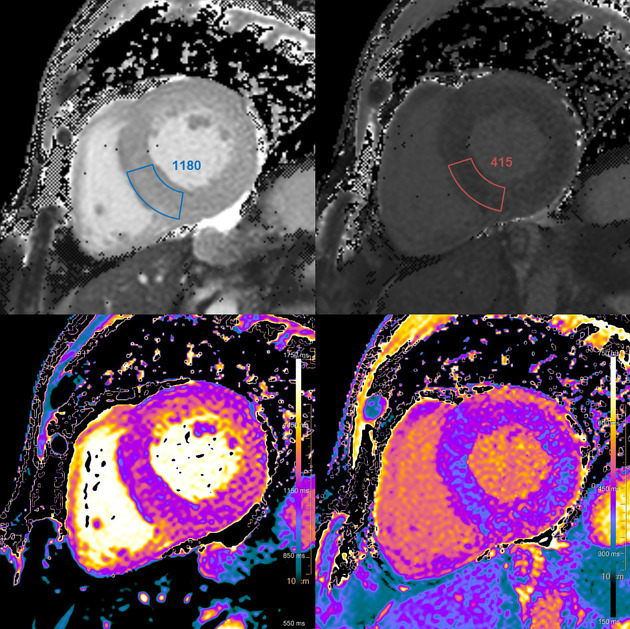

6) 심장 자기공명영상

- 심장자기공명영상 : 민감도가 높은 검사법